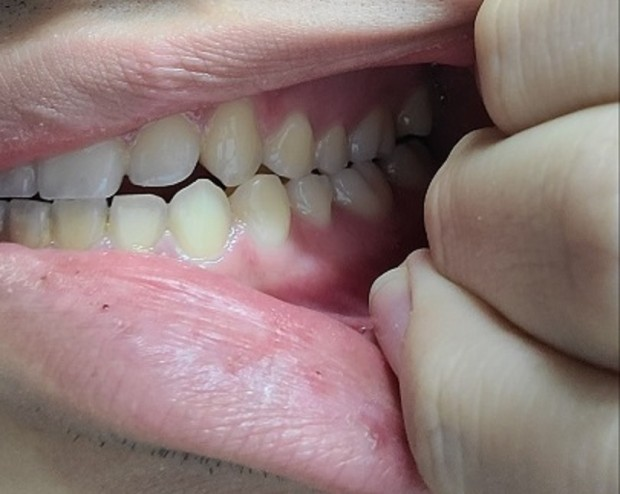

• 2번 째 사진

안녕하세요. 구강악안면외과랑 교정과 돌아봤는데 절단교합인 3급 부정교합이 있고 어금니가 잘 맞지 않는 상태라면서 돌출입 경향에 거미스마일이 있다는 진단과 함께 미세한 비대칭(3mm정도 가량)과 턱끝이 7~8mm(이마뼈 기준 턱 끝이 5mm들어간 위치를 정상으로 볼 때)가량 나왔다는 진단을 받았습니다. 그러면서 발치가 동반되는 돌출입 교정을 하면 주걱턱스러운 부분이 어느정도 개선되지만 중안면부 함몰 및 주걱턱에서 나타나는 중안모가 꺼져서 나타나는 특유의 이상한 느낌에 대한 개선과 하악이 전돌된 부분에 대한 제대로 된 개선​은 어렵다고 했습니다. 그 외의 방법으로의 주걱턱 교정은 외모 개선의 효과는 전혀 없고 교합만 맞춰진다고 했습니다. 그러면서 확실한 외모 개선(중안면부 함몰에 대한 개선과 하악이 전돌된 부분에 대한 개선)을 원한다면 상악의 발치교정으로 위턱이 들어간 상태에서 위턱을 전체적으로 전방이동하는 수술방식 혹은 양악 회전술(전문 용어로 clockwise rotation of maxilla mandibular complex, 이 술식의 경우 하악이 너무 뒤로 이동할 가능성이 높은 술식)과 더불어 이부성형술을 교합만 맞추거나 돌출입만 들어가는 정도로 생각한다면 교정을 생각해보라는 이야기를 들었습니다. 저는 확실한 외모 개선(중안면부 함몰에 대한 개선과 하악이 전돌된 부분에 대한 개선​)을 원하지만 양악수술은 구강악안면외과의 수술 중 비교적 큰 수술에 속하는 만큼 신중히 결정하고자 합니다. 우선 안모, 교합, x-ray 사진자료를 올릴 테니 수술 케이스, 보더라인, 수술 정말 필요없는 케이스 중 어디에 속하는지 대략적인 판단을 부탁드립니다. 선생님 다시 한 번 말씀드리지만 저는 확실한 외모 개선(특히 중안면부 함몰에 대한 개선​)을 원합니다!!!